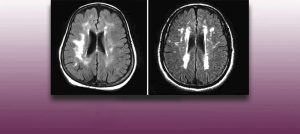

Institut Chiari & Siringomielia & Escoliosis de Barcelona is highly specialized neurosurgical center dedicated to the diagnosis and treatment of spinal and brain disorders, with a focus on the clinical concept of Filum Terminale Disease. Conditions treated include: